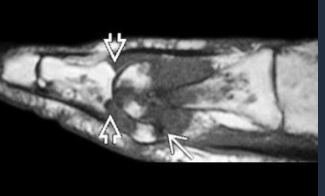

Septic Arthritis (Pseudomonas)

Septic Arthritis MRI

Within 24 hrs from onset

T1: subchondral hyposignal on both bones

Fluid sensitive sequences: hypersignal fluid in joint, surrounding edema

Post contrast:

Synovial enhancement

Subchondral enhancement

Soft tissue abscess

Septic Arthritis US

Small fluid effusions

Thickened synovial membrane + Doppler signal in acute phase

US guided joint punctures (Dg, therapeutic)